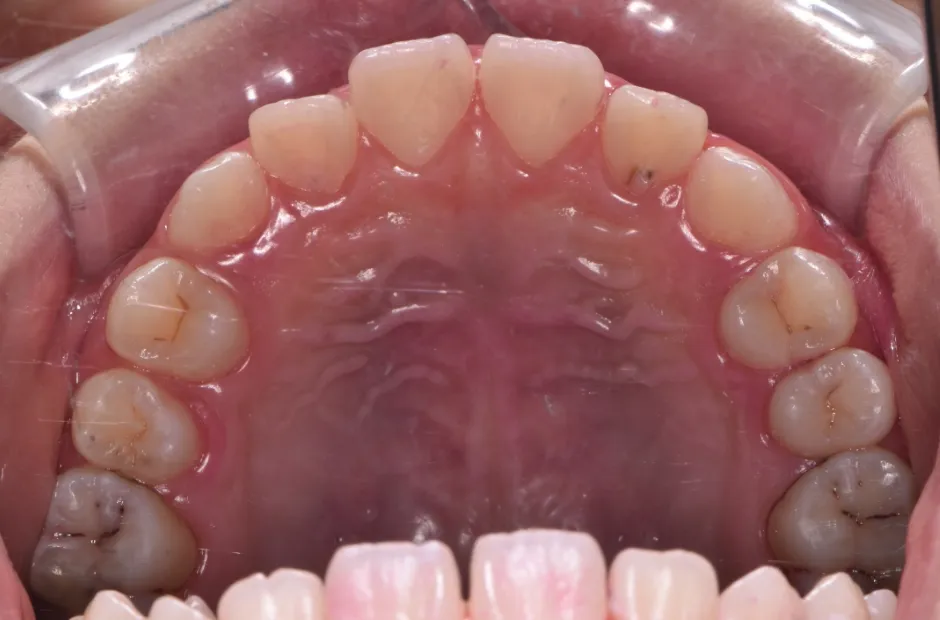

叢生

| 診断名・主訴 | 叢生 |

|---|---|

| 年齢・性別 | 10歳・女性 |

| 治療期間・回数 | 2年半 |

| 治療に用いた主な装置 | 拡大床装置 |

| 抜歯部位 | なし |

| 治療費 | 30万円(税抜) |

| リスク・副作用 | 装置による違和感・疼痛・歯肉退縮・歯根吸収・虫歯のリスクなど |

治療前

治療中

治療後